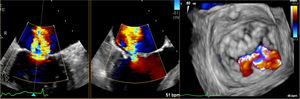

Se acordó implantar un MitraClip (Abbott Vascular, Estados Unidos) (figura 1) a una mujer de 79 años. Se obtuvo el consentimiento informado pertinente. Los intentos de punción transeptal (PTS), mediante una vaina Mullins y una aguja Brockenborough curvada manualmente en diversos ángulos, no dieron resultado debido a una pronunciada tortuosidad venosa. Los intentos de enderezar la vena cava inferior (VCI) con una vaina de calibre 14 Fr fueron infructuosos. Se utilizó entonces un catéter dirigible Agilis de curva media (St. Jude Medical, Estados Unidos) para alcanzar la fosa oval. Se realizó una PTS aplicando una breve descarga de energía de radiofrecuencia (∼ 60W) a una guía Confianza de 0,014” (Asahi Intecc, Estados Unidos). A continuación se introdujo la vaina Agilis en la aurícula izquierda (AI) y se colocaron 2 guías, Amplatz Superstiff y Extrastiff (Boston Scientific, Estados Unidos), en la vena pulmonar superior izquierda. Se retiró la vaina de 14 Fr y, tras dilatar el acceso venoso (18 Fr), se introdujo el catéter guía (CG) dirigible de 24 Fr sobre la guía Superstiff. Sin embargo, seguía siendo imposible atravesar el tabique interauricular (TIA) con el CG debido al poco apoyo y posibilidad de empuje en la VCI tortuosa. Se mantuvo el CG en la aurícula derecha y se introdujo una vaina de calibre 7 Fr sobre la otra guía (Amplatz Extrastiff). A continuación, se realizó una septostomía con balón de angioplastia transluminal percutánea de 10 × 40mm y, tras deshinchar el balón, se introdujo el CG de 24 Fr en la AI (figura 2). Por último, se colocó un MitraClip para tratar un prolapso A2-P2 (figura 3).